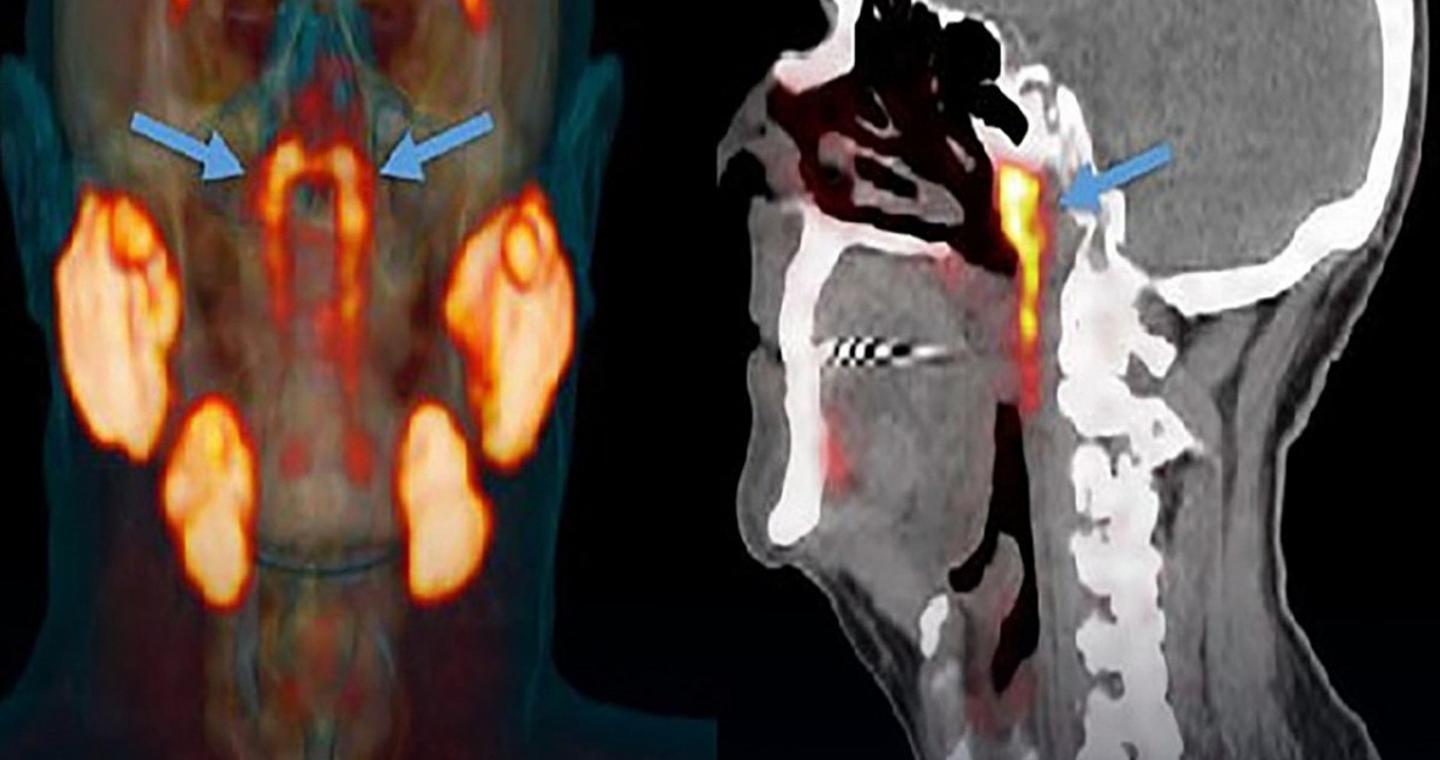

Ο τρόπος με τον οποίο ανακαλύφθηκαν είναι εξίσου εντυπωσιακός: κατά τη διάρκεια εξετάσεων με αξονικές και PET τομογραφίες σε ασθενείς στους οποίους είχαν γίνει ενέσεις με ραδιενεργή γλυκόζη, οι ερευνητές παρατήρησαν δύο φωτεινά σημεία στο κεφάλι. Μετά από περαιτέρω ανάλυση, συμπέραναν ότι επρόκειτο για άγνωστους μέχρι τότε σιελογόνους αδένες.

Πρόκειται για ένα ζεύγος σιελογόνων αδένων, οι οποίοι παρέμεναν «κρυμμένοι» για αιώνες. Οι επιστήμονες τους ονόμασαν tubarial salivary glands (σωληναριακοί σιελογόνοι αδένες). Η λειτουργία τους είναι να λιπαίνουν και να υγραίνουν την περιοχή του λαιμού πίσω από τη μύτη και το στόμα, μια ζωτικής σημασίας λειτουργία για τον οργανισμό.